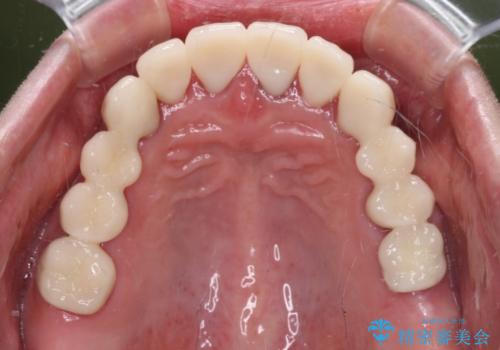

- 歯茎からの出血、入れ歯、歯の欠損、デコボコの前歯などを気にして来院された患者様です。

大の歯科治療嫌いとのことでしたが、今回の治療を契機にしっかりと治療を行いたいとのことでした。

まずは抜歯が必要な歯を抜歯した上で仮歯に置き換え、インプラント埋入や歯周外科処置、根管治療を行うこととしました。

歯肉の状態が落ち着いた後に下顎の矯正治療を行い、その後補綴治療を行うこととしました。

インプラントに対する恐怖心が強く、欠損補綴は極力ブリッジを採用し、インプラントの数は必要最小限としました。

油断をするとすぐに汚れが溜まって歯肉が腫れてきてしまうため、今後も定期的なメインテナンスが重要となります。